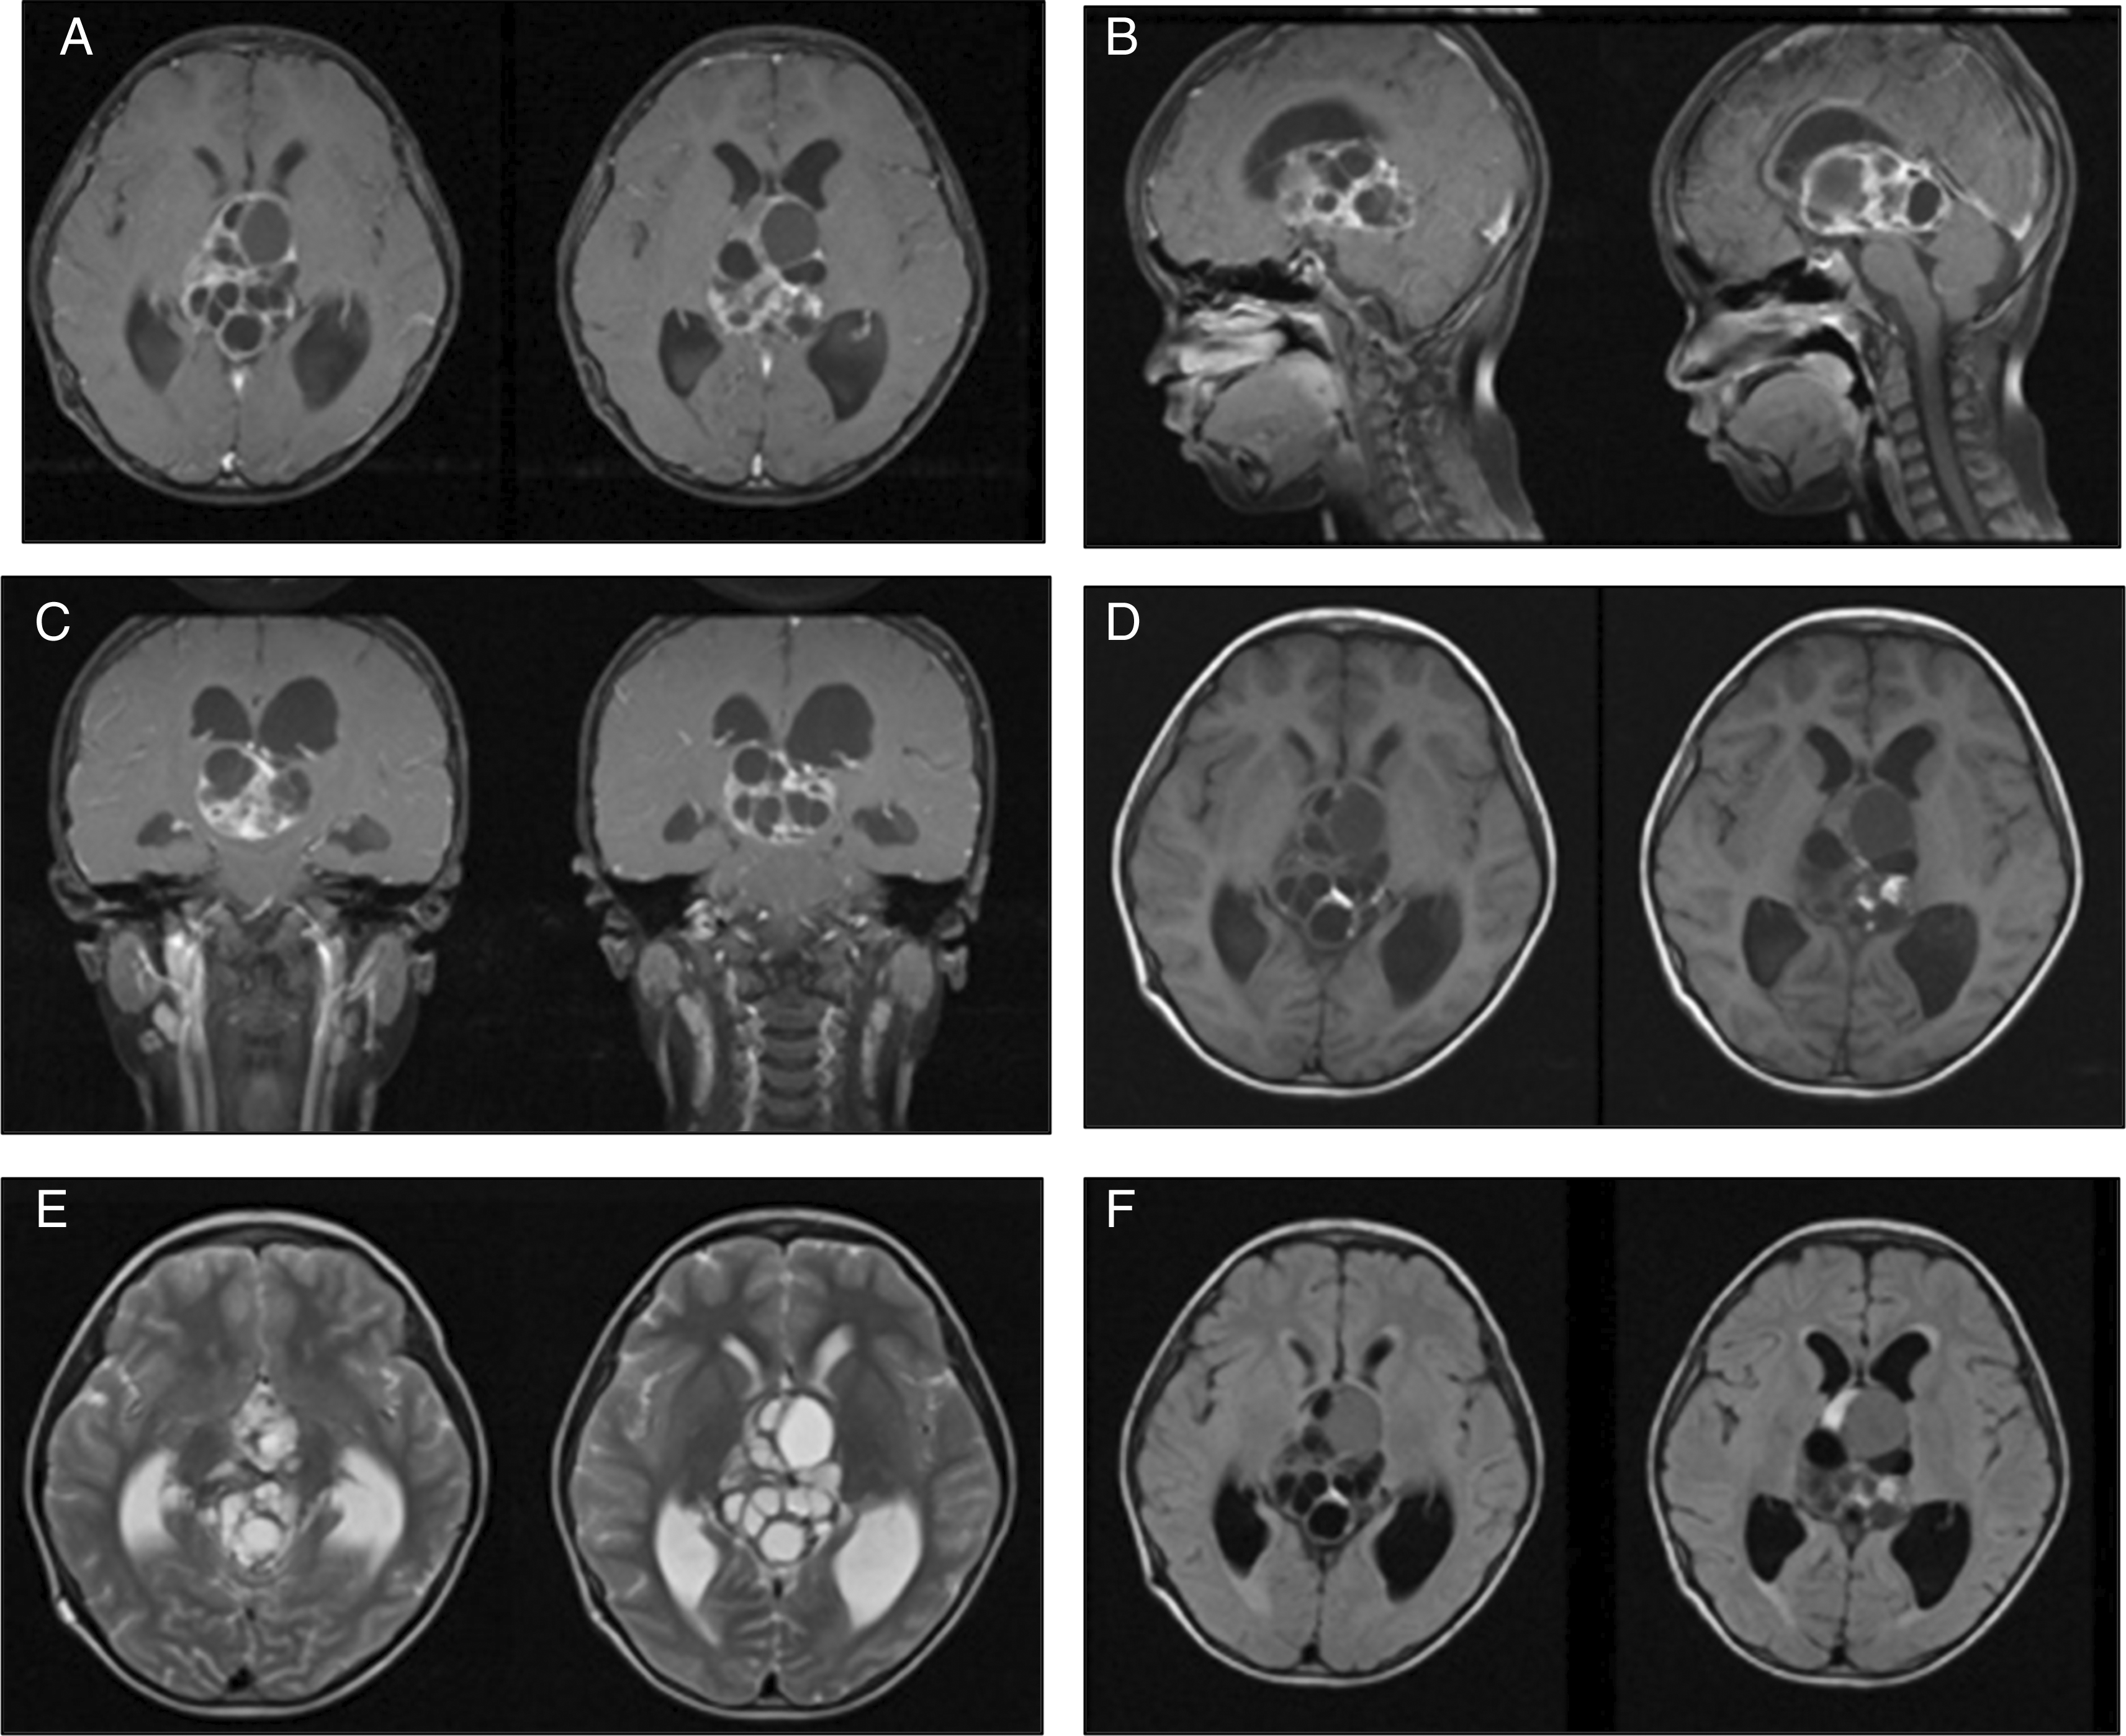

An 8-year-old boy presented to our center with a history of decreased consciousness, generalized seizures, progressive headache, and vomiting one week prior to admission to our hospital. The patient had previously undergone a VP shunt for communicating hydrocephalus because of tuberculous meningitis 1 year prior and clinically improved. He underwent a head CT scan due to this latest clinical deterioration, which showed hydrocephalus with a lobulated cystic and solid mass in the 3rd ventricle. Subsequent contrast-enhanced CT imaging indicated the presence of vascular structures surrounding the tumor. The internal cerebral vein was visible, crossing beneath the tumor (Figure 1). The patient also underwent contrast head MRI, and the result showed a well-defined multiloculated mass with cystic and solid components filling the 3rd Ventricle which was enhanced inhomogenously with gadolinium contrast administration and enlarged lateral ventricles (Figure 2). An endoscopic tumor biopsy was performed, and the histopathological results suggested that the tumor was an arachnoid cyst.

These images showed heterogenous intraventricular multilobulated thick-walled mass with solid and cystic component in T1WI and contrast T1WI imaging (A-D). T2W1 and Flair showed cystic component of the mass with minimal peritumoral edema (E, F).

In terms of imaging modalities, intracranial teratomas often present as single or multiloculated ovoid or lobulated masses. Intracranial teratomas are frequently observed to have fatty components, cystic areas, and calcifications on CT images.13 In MRI, teratomas usually appear as well-defined masses with mixed signals on T1- and T2-weighted images. Fatty and highly proteinaceous material typically appear brighter on T1WI, while calcification and blood are usually darker on both T1WI and T2WI. The cystic, solid, and hemorrhagic regions showed varied signals on T2WI. Gadolinium contrast enhancement is generally heterogeneous.2 Liu et al. (2013) showed that malignant teratomas exhibit significant irregular enhancement on contrast-enhanced T1-weighted images, indicating vascular proliferation in the solid region of the tumor. This marked enhancement is key to differentiating between mature and malignant teratomas.10